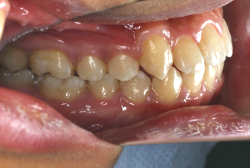

上顎前突

上顎前突(出っ歯)とは上顎が前に出ている状態です。この症状の特徴は、上下の歯並び全体の位置関係が相対的に上顎が優位になっていて、前歯が外に反っているだけでなく奥歯の位置関係も上が前にズレています。さらに凸凹の症状も合併していることがよくあり、上の前歯の見た目を気にして来院する方が多いのですが、実は今言った理由で噛み合わせにも異常があるため、このまま放置すると顎関節症という症状が出ることもあります。

「出っ歯を治したい」という主訴で来院したケースです。診断の結果、「2級1類の上顎前突+軽度叢生」と判明しました。2級というのは、基本的に出っ歯の噛み合わせになっていることを言います。その中でも上の前歯が著しく外に反っているケースを、「1類」といいます。初診時の横向きの写真を見ると、それがはっきり分かります。上の前歯に押されて唇も膨らんで、審美線をかなりオーバーしています(審美線とは、鼻の先端と顎の先端を結ぶ線のことで、この線よりも唇は内側にある方が良いとされています)。

このような症状の場合は、前歯を内側に入れるためにかなり大量の隙間を必要とします。通常は上下左右の小臼歯を抜歯させていただくのが正解です。治療後は歯の角度が正しくなっただけでなく、唇の審美性が大幅に改善しました。もちろん噛み合わせ的にも正しい状態が確立しています。